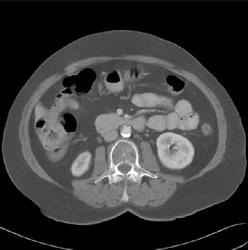

Untagged CT Scan

Tagged CT Scan